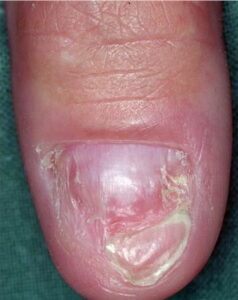

• Solitary glomus tumors have the following characteristics:

• Blue or purple

• Papules or nodules that can be blanched

• Size usually smaller than 1 cm

• Located most commonly in acral areas, especially subungual areas of fingers and toes